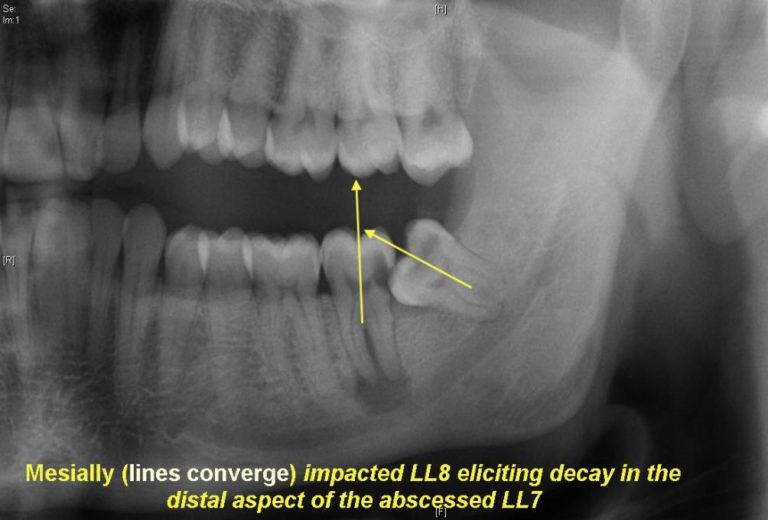

The impaction depth, ramus relationship, and angulation classification

The impaction depth, ramus relationship, and angulation classification What Are Wisdom Teeth Third Molar If an impacted wisdom tooth causes. if a wisdom tooth, also known as a third molar, doesn't have room to grow, it can become impacted. Molars are designed to sustain great amounts of force. Most people have four wisdom teeth — two on the top. wisdom teeth are the third and final set of molars that most people. What Are Wisdom Teeth Third Molar.